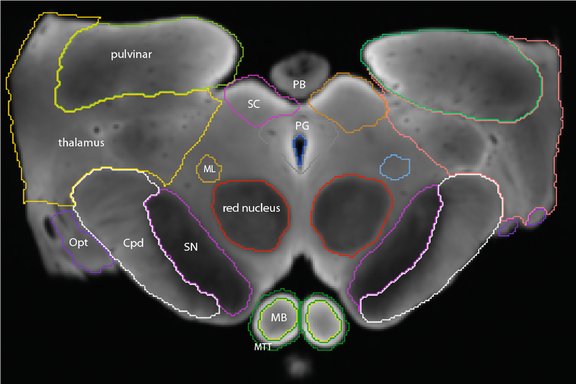

Examples of imaging of the red nucleus and substantia nigra across different field strengths (1.5, 3T, 7T), in vivo or post mortem and with different imaging sequences. Only the two images on the left are acquired in the same person, numbers and outlines indicate labelled structures.